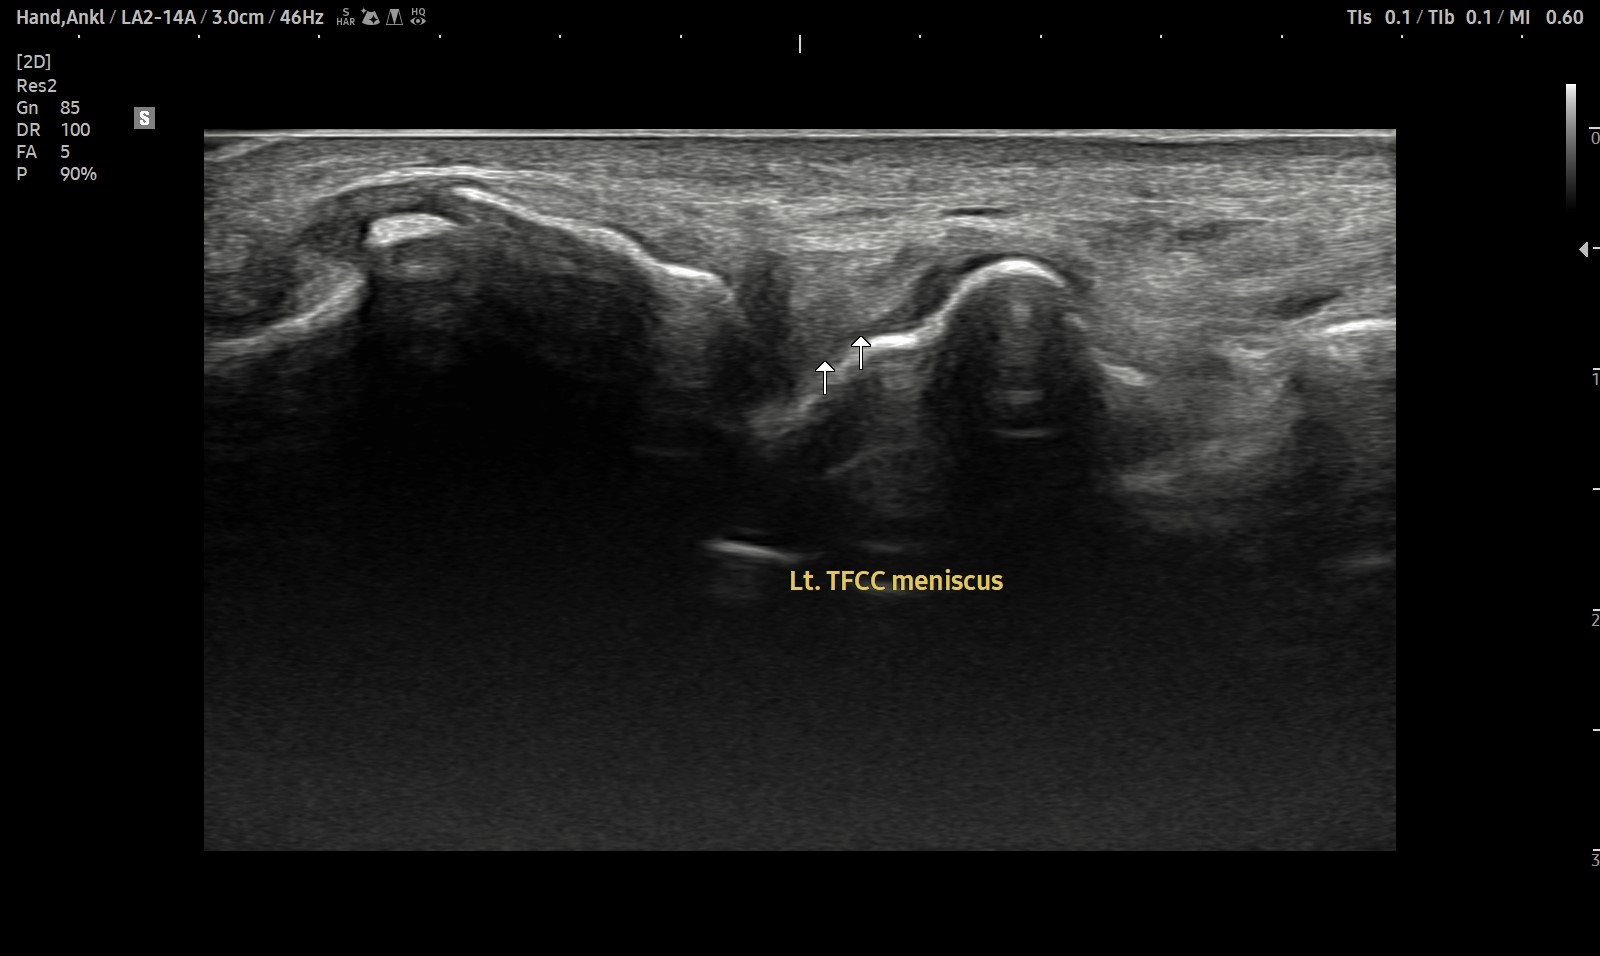

- 치료기간 : 25 . 5 . 7 ~ 25 . 8 .12

- 치료횟수 : 4cycle(20) 회

치료전

치료후